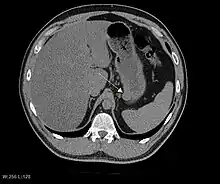

Imaging

The purpose of radiologic imaging is to locate the lesion, evaluate for signs of invasion and detect metastasis. Features of GIST vary depending on tumor size and organ of origin. The diameter can range from a few millimeters to more than 30 cm. Larger tumors usually cause symptoms in contrast to those found incidentally which tend to be smaller and have better prognosis.[4][13] Large tumors tend to exhibit malignant behavior but small GISTs may also demonstrate clinically aggressive behavior.[14]

Barium fluoroscopic examinations and CT are commonly used to evaluate the patient with abdominal complaints. Barium swallow images show abnormalities in 80% of GIST cases.[14] However, some GISTs may be located entirely outside the lumen of the bowel and will not be appreciated with a barium swallow. Even in cases when the barium swallow is abnormal, an MRI or CT scan must follow since it is impossible to evaluate abdominal cavities and other abdominal organs with a barium swallow alone. In a CT scan, abnormalities may be seen in 87% of patients and it should be made with both oral and intravenous contrast.[14] Among imaging studies, MRI has the best tissue contrast, which aids in the identification of masses within the GI tract (intramural masses). Intravenous contrast material is needed to evaluate lesion vascularity.

Preferred imaging modalities in the evaluation of GISTs are CT and MRI,[16]: 20–21 and, in selected situations, endoscopic ultrasound. CT advantages include its ability to demonstrate evidence of nearby organ invasion, ascites, and metastases. The ability of an MRI to produce images in multiple planes is helpful in determining the bowel as the organ of origin (which is difficult when the tumor is very large), facilitating diagnosis.

As the tumor grows it may project outside the bowel (exophytic growth) and/or inside the bowel (intraluminal growth), but they most commonly grow exophytically such that the bulk of the tumor projects into the abdominal cavity. If the tumor outstrips its blood supply, it can necrose internally, creating a central fluid-filled cavity with bleeding and cavitations that can eventually ulcerate and communicate into the lumen of the bowel. In that case, barium swallow may show an air, air-fluid levels or oral contrast media accumulation within these areas.[14][17] Mucosal ulcerations may also be present. In contrast-enhanced CT images, large GISTs appear as heterogeneous masses due to areas of living tumor cells surrounding bleeding, necrosis or cysts, which is radiographically seen as a peripheral enhancement pattern with a low attenuation center.[13] In MRI studies, the degree of necrosis and bleeding affects the signal intensity pattern. Areas of bleeding within the tumor will vary its signal intensity depending on how long ago the bleeding occurred. The solid portions of the tumor are typically low signal intensity on T1-weighted images, are high signal intensity on T2-weighted images and enhanced after administration of gadolinium. Signal-intensity voids are present if there is gas within areas of necrotic tumor.[15][18][19]

Features of malignancy

Malignancy is characterized by local invasion and metastases, usually to the liver, omentum and peritoneum. However, cases of metastases to bone, pleura, lungs and retroperitoneum have been seen. In distinction to gastric adenocarcinoma or gastric/small bowel lymphoma, malignant lymphadenopathy (swollen lymph nodes) is uncommon (<10%) and thus imaging usually shows absence of lymph node enlargement.[13] If metastases are not present, other radiologic features suggesting malignancy include: size (>5 cm), heterogeneous enhancement after contrast administration, and ulcerations.[4][13][20] Also, overtly malignant behavior (in distinction to malignant potential of lesser degree) is less commonly seen in gastric tumors, with a ratio of behaviorally benign to overtly malignant of 3-5:1.[4] Even if radiographic malignant features are present, these findings may also represent other tumors and definitive diagnosis must be made immunochemically.